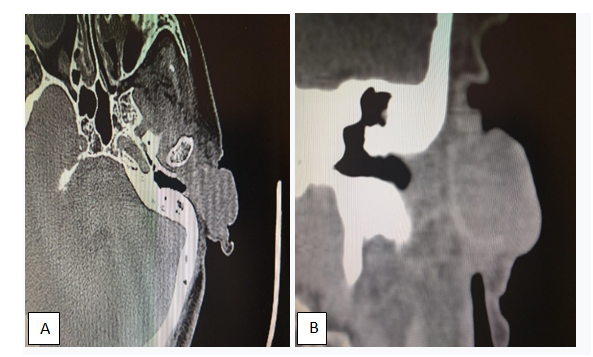

Ears and mastoids tomography (Figure 2) are requested to evaluate the location and tumor extension, it is evident the left auricular tumor with extension to the ear canal. Neck CT scan was lymph nodes free. Patient returns two months later (Figure 3) to do the biopsy with local anesthesia, a greater erythematous tumor size is evident, already occupies the entire conchal bowl and obstructs the left auditory meatus, with a hyperkeratosis center, round edges and small telangiectasias area. The biopsy reports Keratoacanthoma, the similarity between Squamous Cell Carcinoma and Keratoacanthoma is well known and makes a difficult pathological diagnosis, therefore we underwent with tumor excision with oncologic margins (Figures 4). Oncologic resection was complete, includes skin and cartilage (Figures 4). Once the tumor is carefully excised it is sent for pathological analysis and diagnosis. The flap reconstruction (posterior island flap) begins once the tumor excision culminates, taking into consideration the size of the tumor and its difficult approach.

Figure 2 Axial computed tomography, (A) it demonstrated left ear hypodense expansive tissue with inadequate contrast capture. (B) Shows conchal bowl soft tissue that occupies the anterior third of the external auditory canal without bone infiltration.